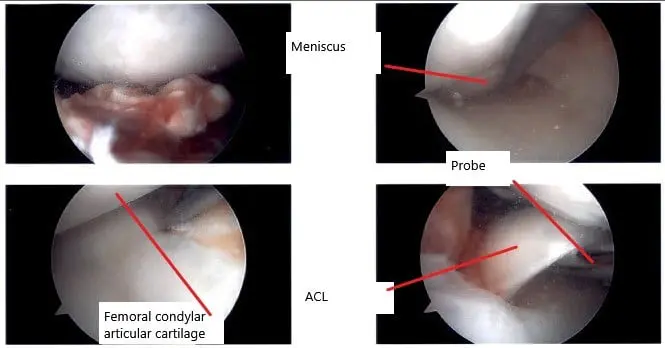

Intraoperative arthroscope image of the right knee.

The arthroscope was entered through the lateral entry portal. Examination of the patellofemoral compartment showed no arthritic changes. Examination of the medial patellofemoral compartment showed grade 3 to grade 4 change in a small patch over the medial femoral condyle. The meniscus showed an inferior flap over the posterior horn, which was removed with the shaver. There was no ramp lesion or meniscal tear. The scope was entered into the intercondylar notch where the ACL was found to be torn.

The ACL was debrided with the use of a shaver. The PCL was intact. The medial wall of the lateral femoral condyle was cleaned and debrided for identification of the footprint of the ACL. The tibial footprint of the ACL was also debrided. The arthroscope was entered into the lateral femoral condyle and lateral tibiofemoral compartment.

It showed grade 3 to grade 4 arthritic changes over a third of the femoral condyle. Also, there was a bad tear in the lateral meniscus, which was extending from the mid-body to the posterior body and the posterior horn across the popliteal hiatus.

The meniscus was not repairable. So, it was debrided with the use of shaver and biters. Balanced edges were obtained at the end of the meniscectomy. Debridement of the lateral femoral condyle was also performed. Now, a PassPort cannula was entered through the medial portal. Lateral femoral zig was used to make an entry canal for the femoral tunnel. A FlipCutter was used and a 25 mm canal was made using the FlipCutter in a usual fashion.